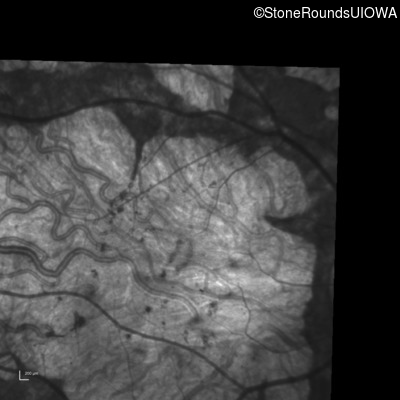

Infrared Fundus Photograph - Right - 10/125 sc

Exemplar